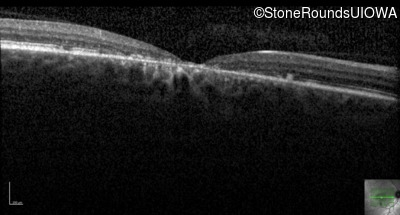

Optical Coherence Tomography - Right - 20/125

Exemplar / OCT Stack

OCT Stack